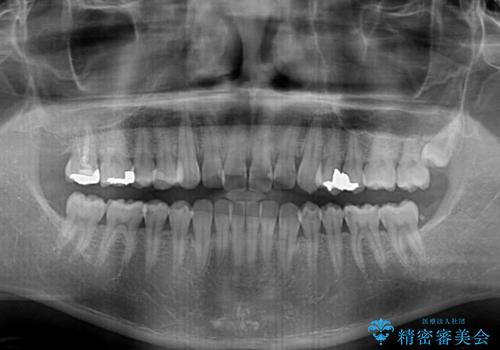

- 上下前歯の叢生を気にして来院された患者様です。

費用を抑え、期間もあまりかけずに治療をしたいとのことで、インビザライン・ライトを用いて矯正治療を行うこととしました。